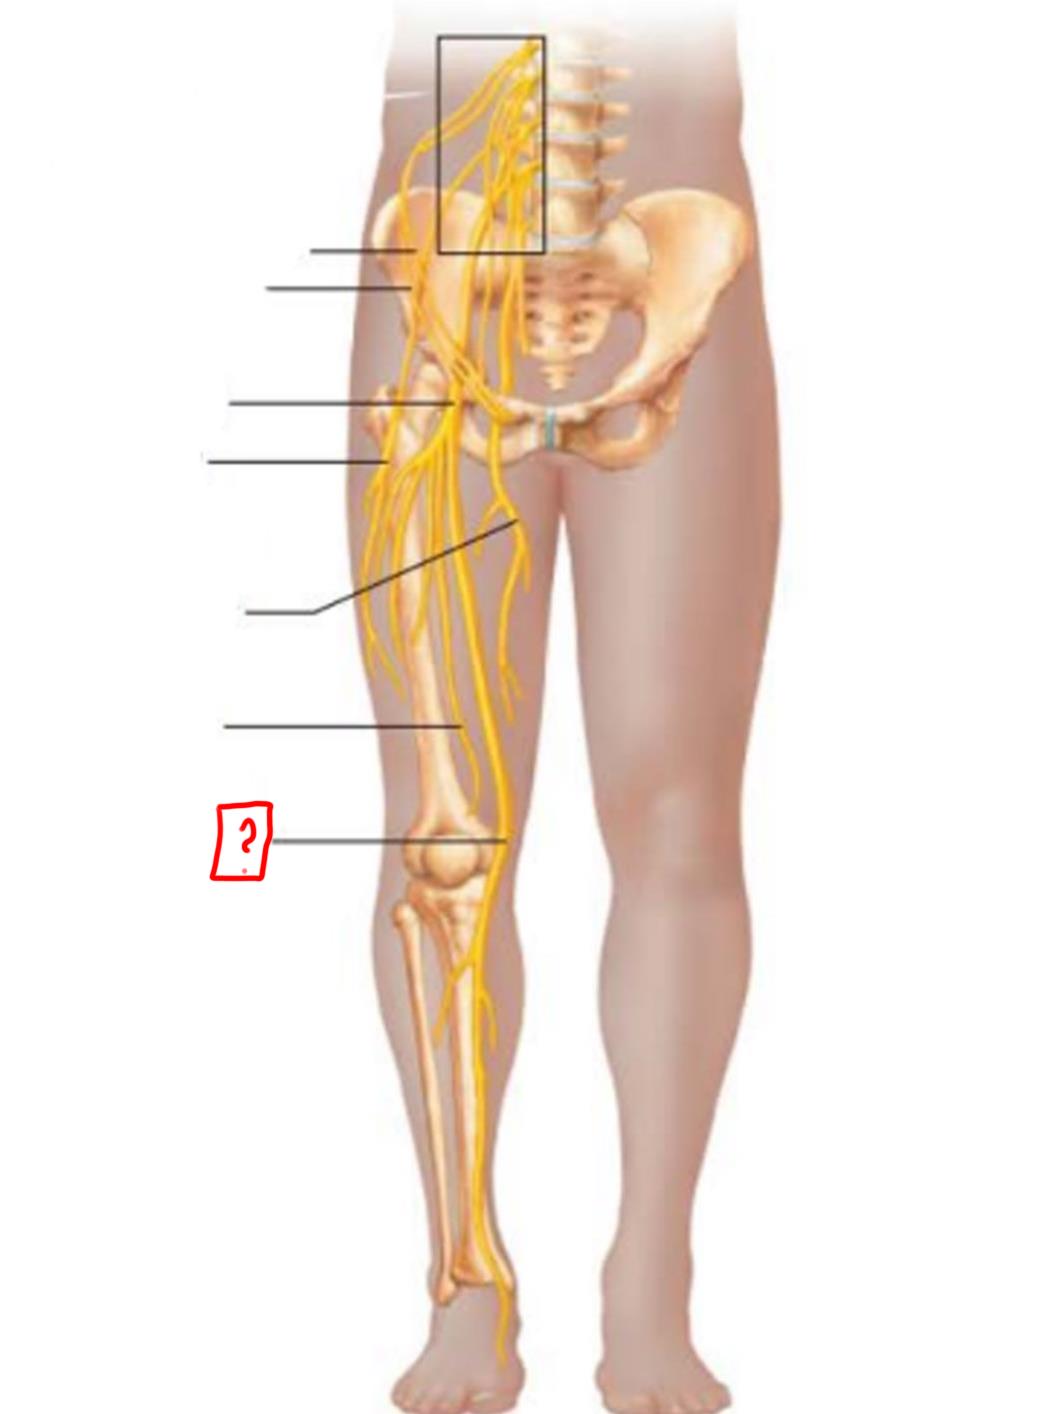

femoral

anterior femoral cutaneous

saphenous